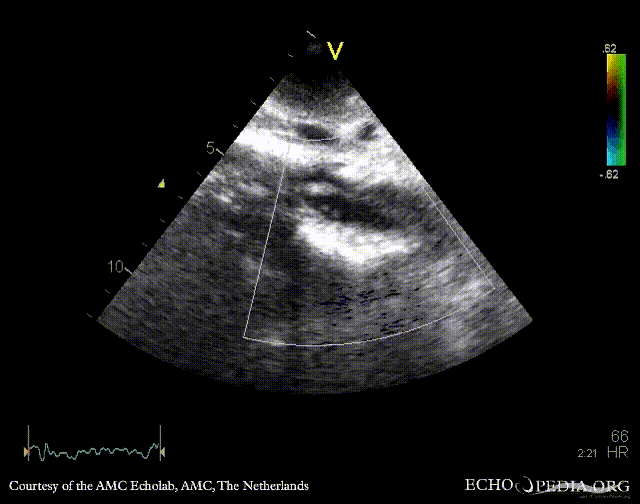

Subcostal view: mobile structure (thrombus) in abdominal aorta